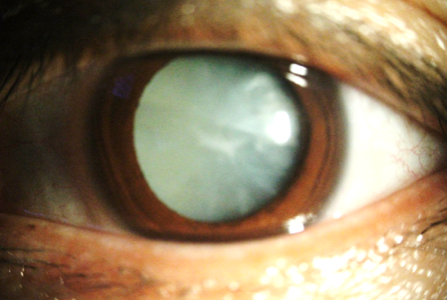

한국은 첨단 백내장 수술 기술과 최첨단 의료 시설로 유명합니다. 가장 일반적으로 수행되는 시술은 초음파 에너지를 사용하여 백내장을 제거하기 전에 분해하는 침습적 방법인 체액유화입니다. 그런 다음 자연 렌즈를 인공 안구 렌즈로 교체합니다. 다초점 또는 토릭 렌즈와 같은 프리미엄 IOL 옵션을 사용하여 노안이나 난시를 교정할 수 있어 안경 없이도 환자에게 더 선명한 시력을 제공할 수 있습니다. 한국 백내장 수술의 장점 중 하나는 접근성입니다. 전국의 클리닉과 병원은 최신 기술을 갖추고 있으며, 많은 병원에서 개인의 요구에 맞는 맞춤형 치료를 제공합니다. 또한 일반적으로 30분 이내에 수술이 완료되고 입원이 필요하지 않아 빠른 회복이 가능합니다. 보험 적용 범위와 관련하여 백내장 수술은 기본 렌즈 교체에 대해 한국의 국민건강보험에서 보장합니다. 그러나 프리미엄 렌즈 옵션 및 관련 비용은 본인 부담금이 필요할 수 있습니다. 많은 사람들이 이러한 추가 비용을 충당하기 위해 추가 건강 보험(특히 실비 보험)을 선택합니다. 이러한 유형의 개인 보험은 재정적 부담을 크게 줄여 프리미엄 렌즈 옵션을 더 부담이 없게 만들 수 있습니다. 수술 전에 의료 전문가 및 보험 회사와 상의하여 보장 내용과 예상되는 본인 부담금에 대해 명확하게 알아보아야 합니다. 백내장은 노화의 피할 수 없는 질병처럼 보일 수 있지만 조기 발견, 적절한 치료, 예방 치료를 통해 삶의 질을 유지할 수 있습니다. 한국은 세계 최고의 건강 보험 체계를 갖추고 있고 세계적 수준의 백내장 수술 기술도 가지고 있기 때문에 환자가 명확한 시력을 갖고 회복하는데 어렵지 않습니다. 증상, 치료 방법 및 보험 보장 범위에 대한 정보를 계속 공부함으로써 눈 건강을 관리하고 더 밝고 명확한 미래를 보장할 수 있습니다.